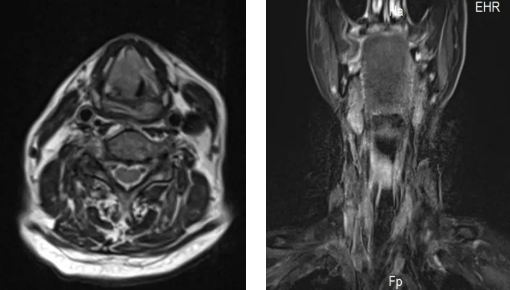

84歲的趙大爺因喉部腫瘤,三個月前做了氣道改造手術,平時靠一根氣管套管輔助呼吸。沒想到一天深夜,這根“生命管”突然脫落,頸部的人工氣道口也很快閉合。老人呼吸困難,被家人緊急送往隨州市中心醫(yī)院。

情況萬分危急,趙大爺呼吸急促,只能坐著喘氣,臉色因缺氧逐漸發(fā)青。耳鼻咽喉頭頸外科主任蔡奇山接到通知后火速趕到。檢查發(fā)現(xiàn),原先的呼吸通道已經堵閉,必須立即手術重建氣道。

時間就是生命。在征得家屬同意后,凌晨的手術室里展開了一場生命接力。蔡奇山帶領團隊緊急為趙大爺進行了喉部腫瘤切除和永久性氣道重建手術。經過四個多小時的全力搶救,手術順利完成。趙大爺?shù)暮粑匦马槙?,脫離了生命危險。在重癥監(jiān)護室觀察穩(wěn)定后,他已轉回耳鼻咽喉頭頸外科病房繼續(xù)康復治療,目前恢復情況良好。